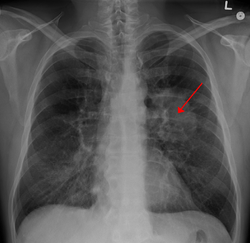

| A chest X-ray showing a tumor in the lung (marked by arrow) | |

The vast majority (85%) of cases of lung cancer are due to long-term tobacco smoking.[7] About 10–15% of cases occur in people who have never smoked.[8] These cases are often caused by a combination of genetic factors and exposure to radon gas, asbestos, second-hand smoke, or other forms of air pollution.[9][7][10][11] Lung cancer may be seen on chest radiographs and computed tomography (CT) scans.[1] The diagnosis is confirmed by biopsy which is usually performed by bronchoscopy or CT-guidance.[12][13]

Performing a chest radiograph is one of the first investigative steps if a person reports symptoms that may suggest lung cancer. This may reveal an obvious mass, widening of the mediastinum (suggestive of spread to lymph nodes there), atelectasis (collapse), consolidation (pneumonia) or pleural effusion.[1] CT imaging is typically used to provide more information about the type and extent of disease. Bronchoscopy or CT-guided biopsy is often used to sample the tumor for histopathology.[13]

Lung cancer often appears as a solitary pulmonary nodule on a chest radiograph. However, the differential diagnosis is wide. Many other diseases can also give this appearance, including metastatic cancer, hamartomas, and infectious granulomas such as tuberculosis, histoplasmosis and coccidioidomycosis.[61] Lung cancer can also be an incidental finding, as a solitary pulmonary nodule on a chest radiograph or CT scan done for an unrelated reason.[62] The definitive diagnosis of lung cancer is based on histological examination of the suspicious tissue[6] in the context of the clinical and radiological features.[12]